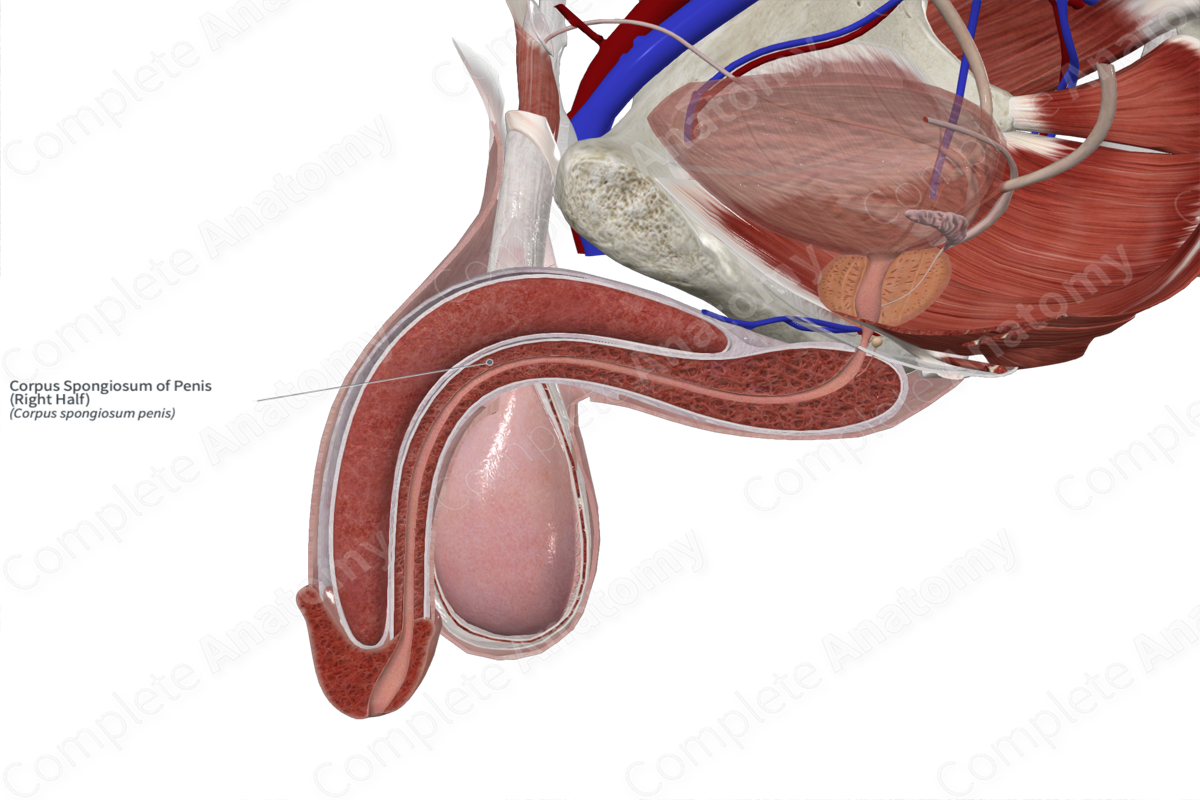

Definition of corpus spongiosum NCI Dictionary of Cancer Terms NCI on sale, Corpus spongiosum penis Wikipedia on sale, Corpus spongiosum penis anatomy Britannica on sale, Corpus cavernosum penis Wikipedia on sale, Corpus Spongiosum of Penis Right Half Complete Anatomy on sale, Corpus spongiosum penis anatomy Britannica on sale, What is the Difference Between Corpus Cavernosum and Corpus on sale, Anatomy corpora cavernosa and spongiosum note the rather large on sale, Corpus Spongiosum StoryMD on sale, Corpus spongiosum penis Wikipedia on sale, Penis Brandywine Urology Consultants on sale, The Penis Structure Muscles Innervation TeachMeAnatomy on sale, SEER Training Penis on sale, Corpus Spongiosum of Penis Left Half Complete Anatomy on sale, Corpus spongiosum penis on sale, Corpus spongiosum Location Functions and Pictures Bodterms on sale, Corpus spongiosum of penis e Anatomy IMAIOS on sale, 3d rendered medically accurate illustration of the corpus on sale, Corpus Spongiosum of Penis Left Half Complete Anatomy on sale, Corpus Spongiosum 6 by Sebastian Kaulitzki science Photo Library on sale, How to identify priapism Medmastery on sale, Penis Anatomy Histology Histology Flashcards ditki medical on sale, Penis Radiology Reference Article Radiopaedia on sale, Corpus spongiosum Location Function Problems and Pictures on sale, Corpus spongiosum hi res stock photography and images Alamy on sale, Hypothesis that urethral bulb corpus spongiosum plays an active on sale, Corpus spongiosum is a part ofA. OvaryB. TestisC. UterusD. Male on sale, Normal penile anatomy. a Drawing axial view illustrates the on sale, 64 Corpus Spongiosum Royalty Free Photos and Stock Images on sale, Symptomatic corpus spongiosum defect in adolescents and young on sale, Corpus Spongiosum 10 by Sebastian Kaulitzki science Photo Library on sale, Corpus Spongiosum Penis Anatomy Function Diagram Body Maps on sale, urethra and corpus spongiosum Histologia on sale, Corpus cavernosum penis Wikipedia on sale, Tissue 177 Penile Urethra and Corpus Spongiosum on sale.

Definition of corpus spongiosum NCI Dictionary of Cancer Terms NCI on sale, Corpus spongiosum penis Wikipedia on sale, Corpus spongiosum penis anatomy Britannica on sale, Corpus cavernosum penis Wikipedia on sale, Corpus Spongiosum of Penis Right Half Complete Anatomy on sale, Corpus spongiosum penis anatomy Britannica on sale, What is the Difference Between Corpus Cavernosum and Corpus on sale, Anatomy corpora cavernosa and spongiosum note the rather large on sale, Corpus Spongiosum StoryMD on sale, Corpus spongiosum penis Wikipedia on sale, Penis Brandywine Urology Consultants on sale, The Penis Structure Muscles Innervation TeachMeAnatomy on sale, SEER Training Penis on sale, Corpus Spongiosum of Penis Left Half Complete Anatomy on sale, Corpus spongiosum penis on sale, Corpus spongiosum Location Functions and Pictures Bodterms on sale, Corpus spongiosum of penis e Anatomy IMAIOS on sale, 3d rendered medically accurate illustration of the corpus on sale, Corpus Spongiosum of Penis Left Half Complete Anatomy on sale, Corpus Spongiosum 6 by Sebastian Kaulitzki science Photo Library on sale, How to identify priapism Medmastery on sale, Penis Anatomy Histology Histology Flashcards ditki medical on sale, Penis Radiology Reference Article Radiopaedia on sale, Corpus spongiosum Location Function Problems and Pictures on sale, Corpus spongiosum hi res stock photography and images Alamy on sale, Hypothesis that urethral bulb corpus spongiosum plays an active on sale, Corpus spongiosum is a part ofA. OvaryB. TestisC. UterusD. Male on sale, Normal penile anatomy. a Drawing axial view illustrates the on sale, 64 Corpus Spongiosum Royalty Free Photos and Stock Images on sale, Symptomatic corpus spongiosum defect in adolescents and young on sale, Corpus Spongiosum 10 by Sebastian Kaulitzki science Photo Library on sale, Corpus Spongiosum Penis Anatomy Function Diagram Body Maps on sale, urethra and corpus spongiosum Histologia on sale, Corpus cavernosum penis Wikipedia on sale, Tissue 177 Penile Urethra and Corpus Spongiosum on sale.